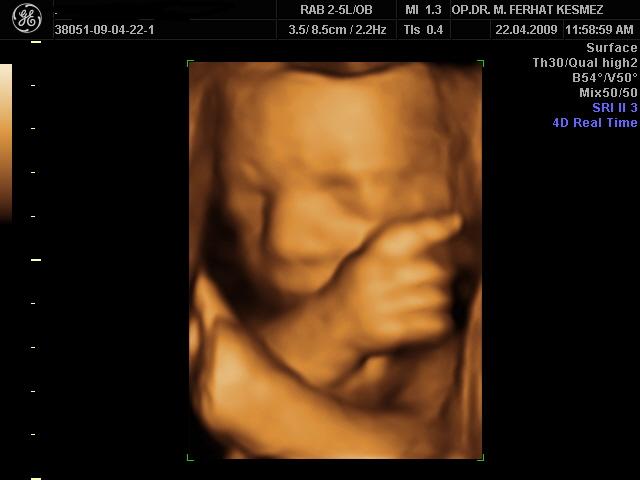

Op. Dr. Muhammed Ferhat Kesmez

Kadın Hastalıkları, Doğum ve Tüp Bebek Uzmanı

• Op. Dr. Muhammed Ferhat Kesmez, kadın sağlığı, gebelik takibi, doğum ve tüp bebek tedavisi alanlarında uzmanlaşmış deneyimli bir hekimdir. Kısırlık (infertilite) tedavisinde en son teknolojileri kullanarak çiftlere anne-baba olma yolculuklarında rehberlik eder. Bireysel ve bilimsel yaklaşımlarla hastalarına özel tedavi yöntemleri sunarak sağlıklı gebelik süreçleri sağlamayı hedefler. Güvenilir ve hasta odaklı hizmet anlayışıyla, modern tıbbın sunduğu yenilikleri hastalarına ulaştırmaktadır.